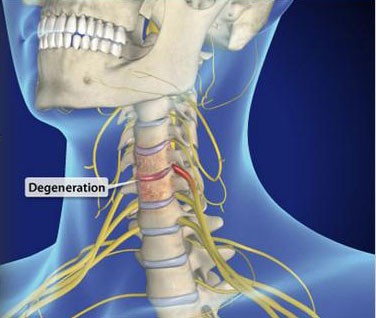

Neck pain is a frequent issue for people affected by poor posture. It can also stem from overuse, wear and tear, injury, and many other potential factors. It can be challenging to recover from intense neck pain without the right professional help. We offer pain management and treatment options that can help to make life enjoyable and pain free once again.